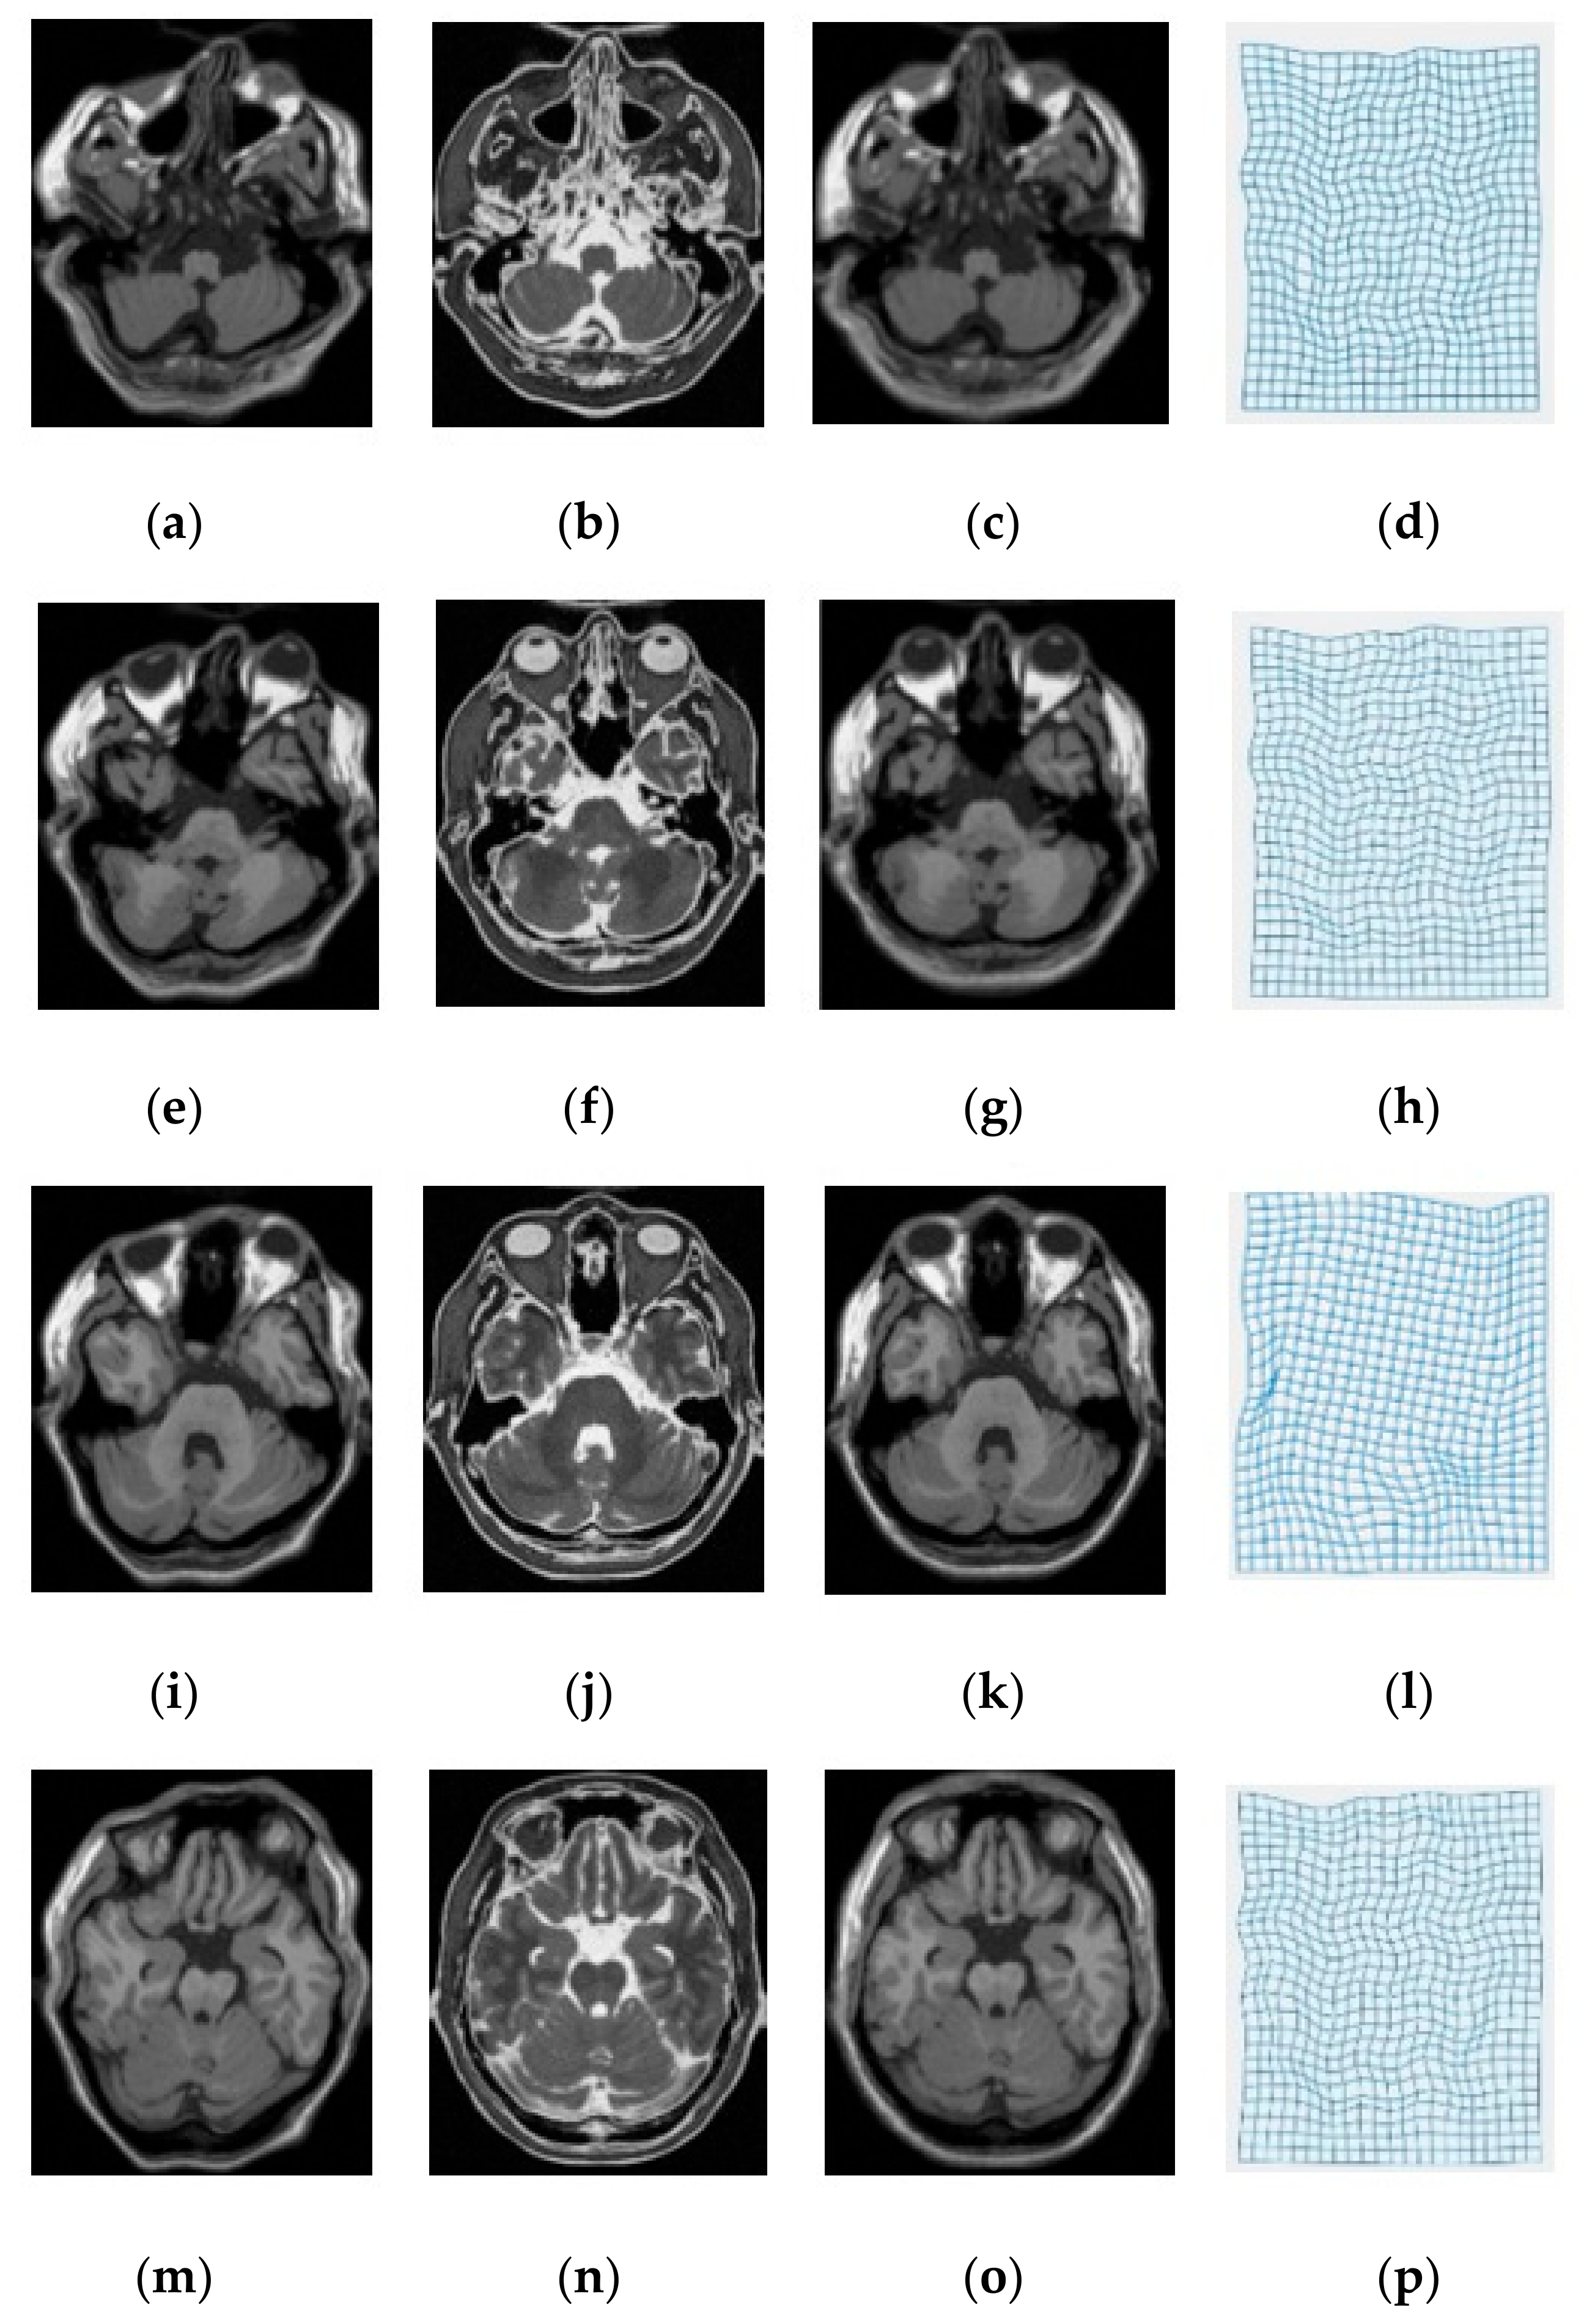

3. Experimental Results and Discussion

| Modality | MI [6] | SSC [21] | miLBP [25] | Ssesi [23] | miRID |

|---|---|---|---|---|---|

| T1-T2 | 2.92 | 2.86 | 2.16 | 2.09 | 1.86 |

| T1-PD | 2.68 | 2.43 | 2.23 | 1.53 | 1.62 |

| T2-PD | 2.94 | 2.86 | 2.47 | 2.05 | 1.98 |

| Average TRE | 2.85 | 2.72 | 2.29 | 1.89 | 1.82 |

| Average Time | 35.2 s | 34.1 s | 24.9 s | 31.7 s | 26.1 s |